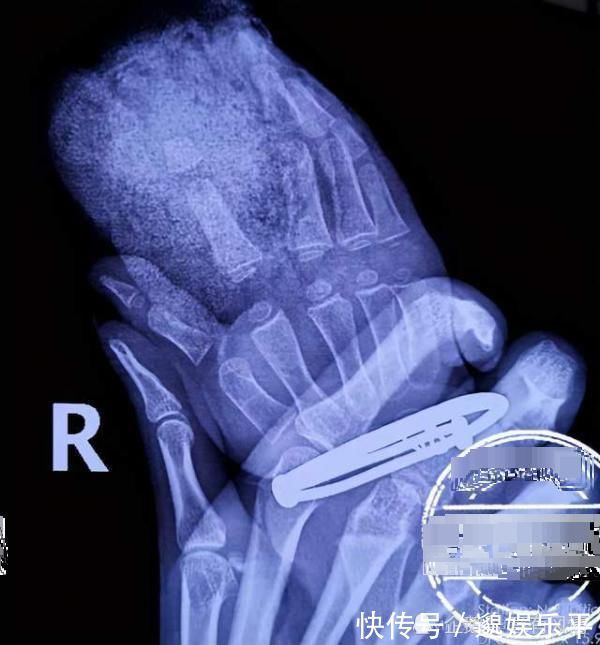

2岁的孩子活泼好动,家长一时疏忽大意就可能发生意外。吉安的陈女士稍不留神,结果两岁的女儿摸上切割机,孩子右手食指是直接被切断。

意外发生后,陈女士赶紧带着2岁大的女儿从吉安老家赶到南昌接受治疗。孩子的主治医生告诉采访人员,孩子的第二个手指在中间位置完全被割断,他们打算给孩子伤口清创后将断指接回去。因为孩子的神经等组织结构相比成人都更加细小,所以为2岁的患者做手指再植手术难度也不小。

医生表示,如果孩子术后恢复好的话,对手指功能影响不是很大。但神经的恢复有个过程,

需要半年到一年以后,刚开始孩子手指肯定是没有感觉的。